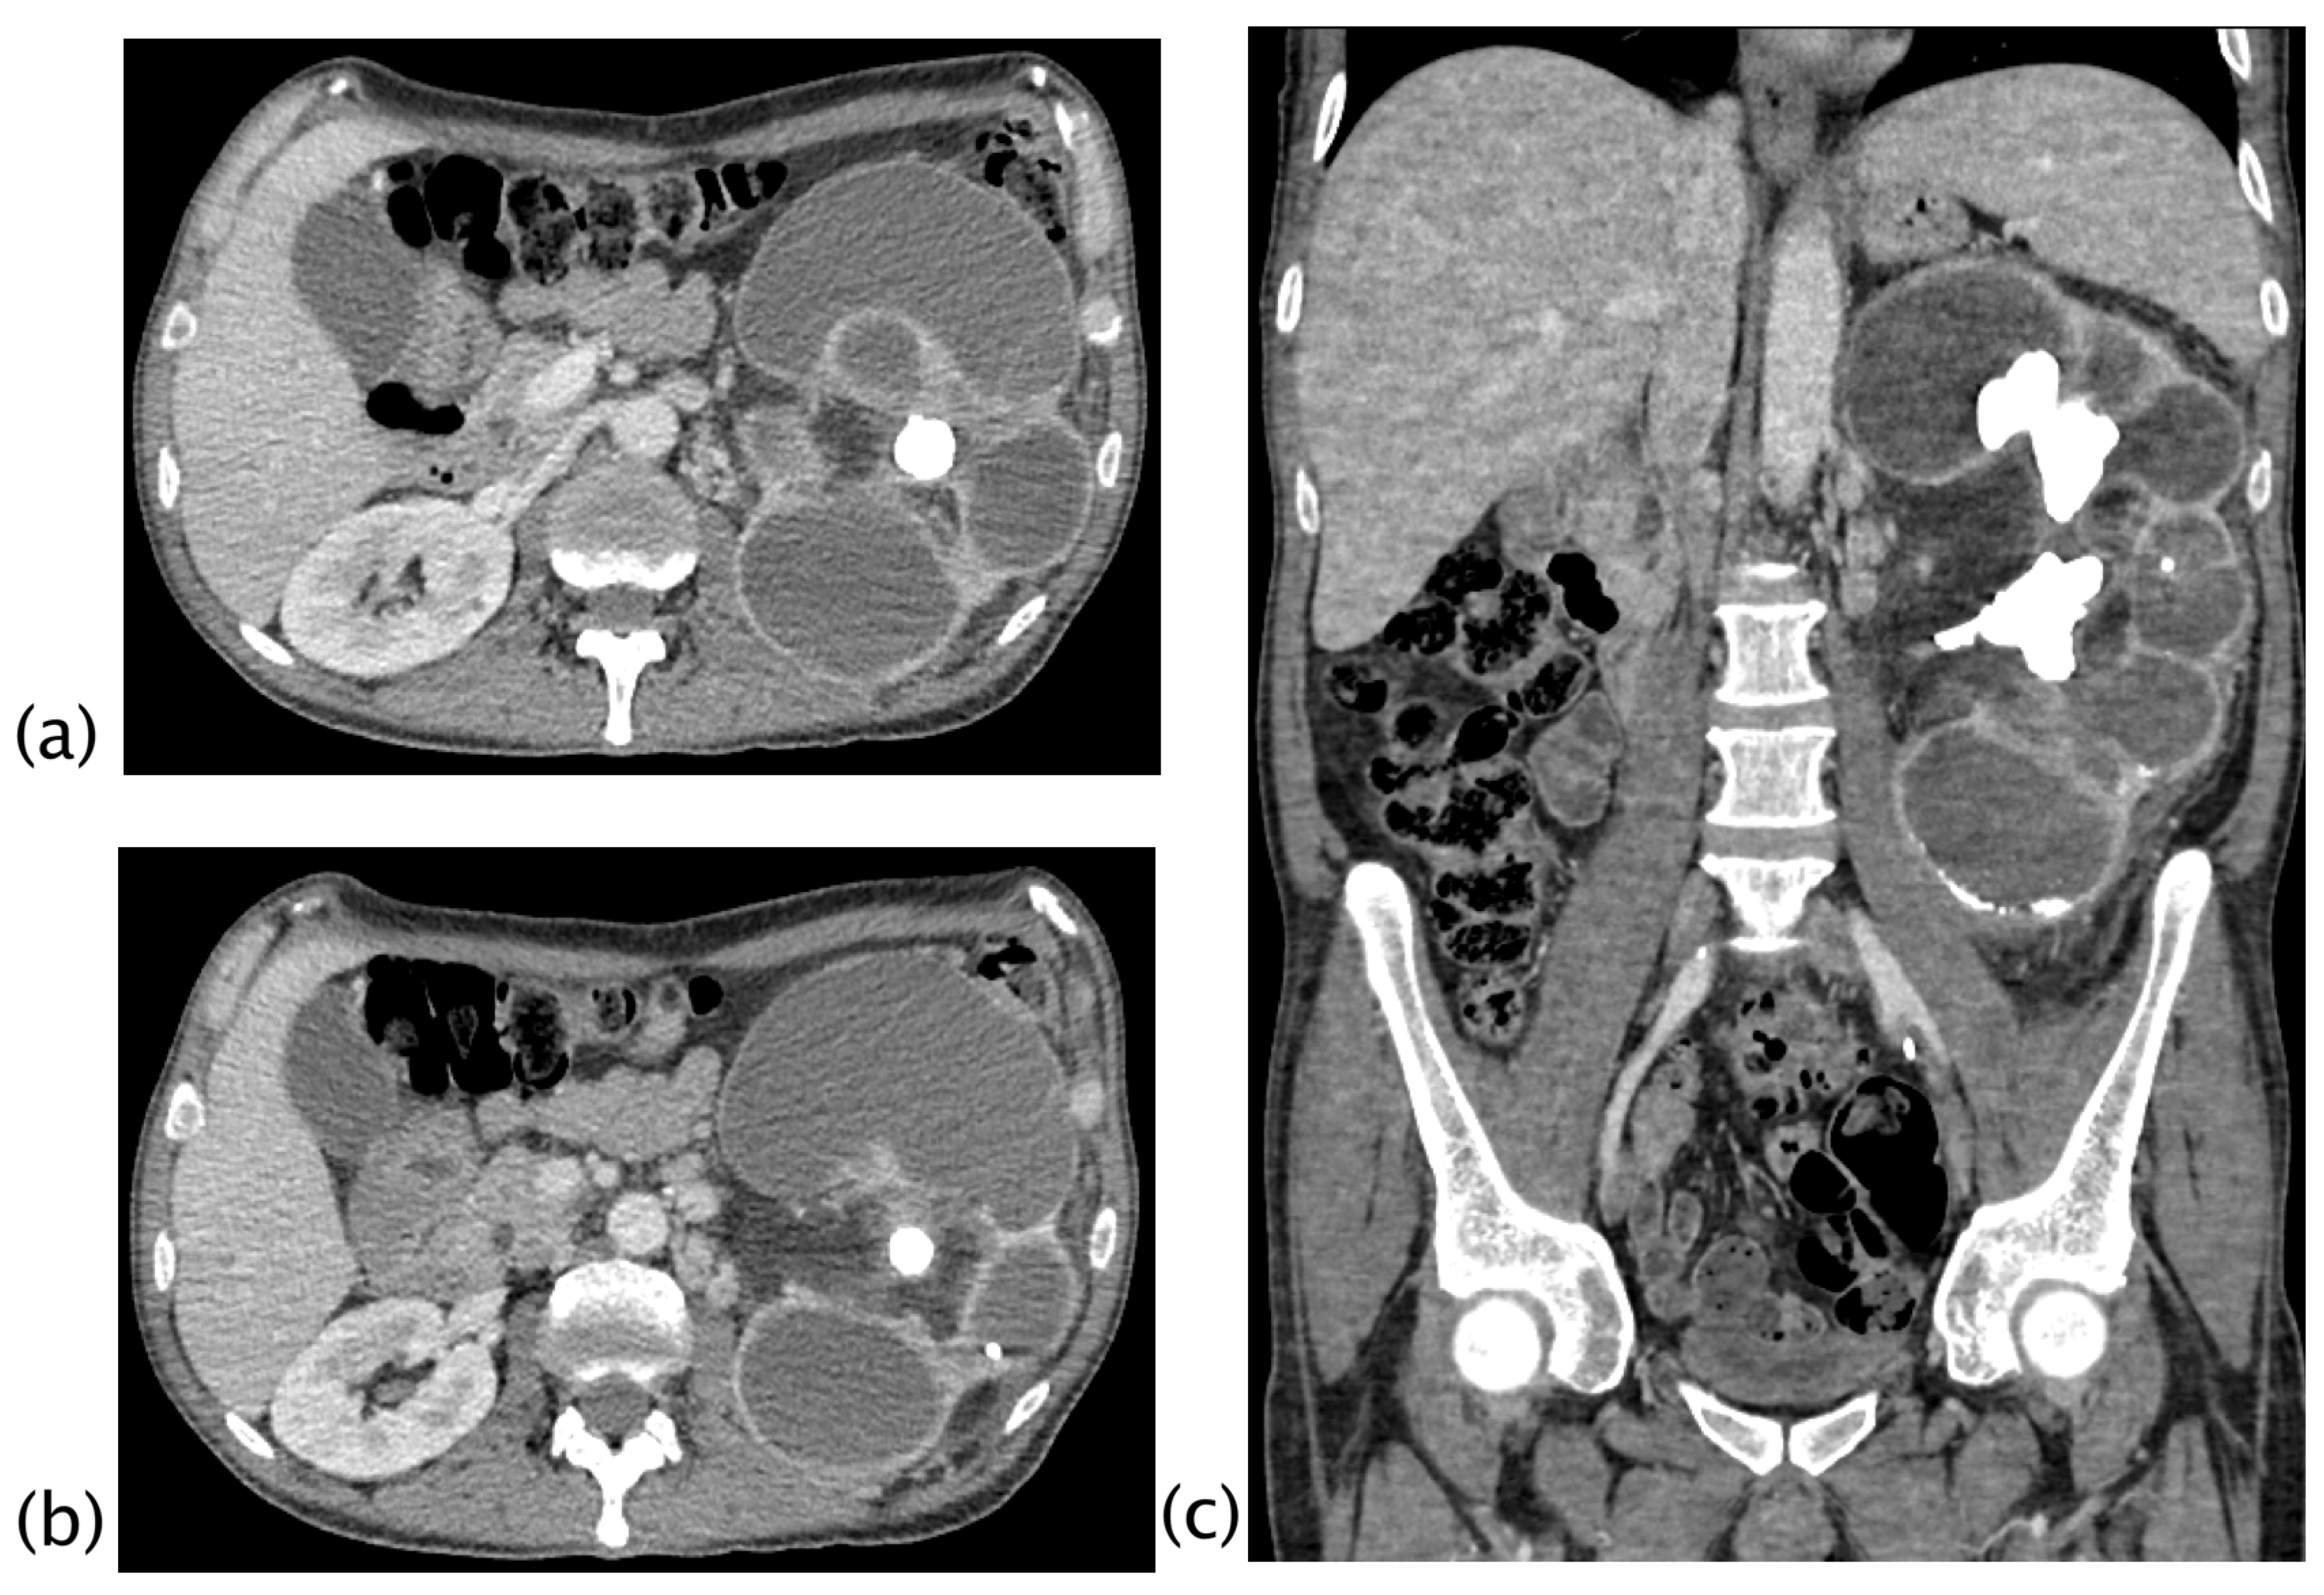

Figure 3.

Xanthogranulomatous pyelonephritis Stage I—nephritic form. CT with contrast agent: axial (a,b) and coronal MPR reconstruction (c). The left kidney is increased in volume with a characteristic “contracted” appearance of the renal pelvis. The renal parenchyma is extremely thinned and characterized by the presence of multiple hypodense areas representing both intraparenchymal collections of pus and dilated calyces. The wall of the pyelocaliceal structures is thickened and hyperemic due to granulation tissue and parenchymal compression caused by abscess cavities. Staghorn lithiasis is present. Perirenal fat is thickened but no peri- or pararenal collections are present. No fistulas or abscesses are evident. The characteristic “bear paw sign” and contracted appearance of the pelvis allowed for the diagnosis of XGP, confirmed on histologic examination. The “bear paw sign” was appreciated on the CT scan in 66.67% of patients.